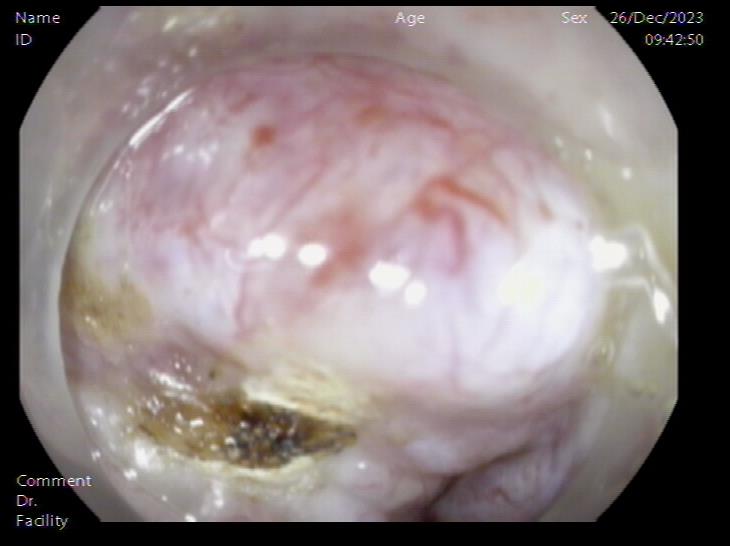

腹腔内囊肿 腹腔内囊肿近景

囊肿切开引流,囊壁塌陷 内镜下胃壁全层缝合